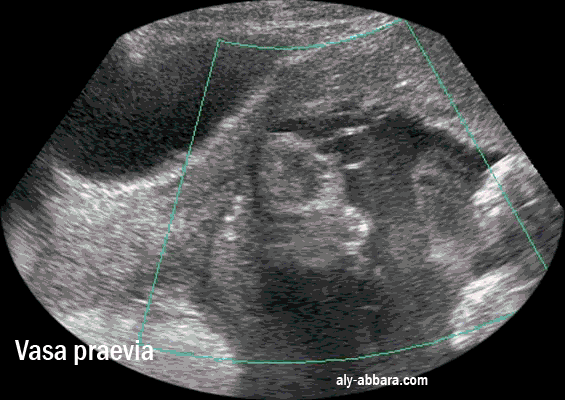

Placenta praevia antérieur type I

avec cotylédon aberrant bas inséré, postérieur de Type II

et en enfin des vaisseaux prævia

(vasa praevia)

reliant le placenta au cotylédon aberrant et bien mis en évidence par Doppler-Dynamic-Flow

35 semaines d'aménorrhée